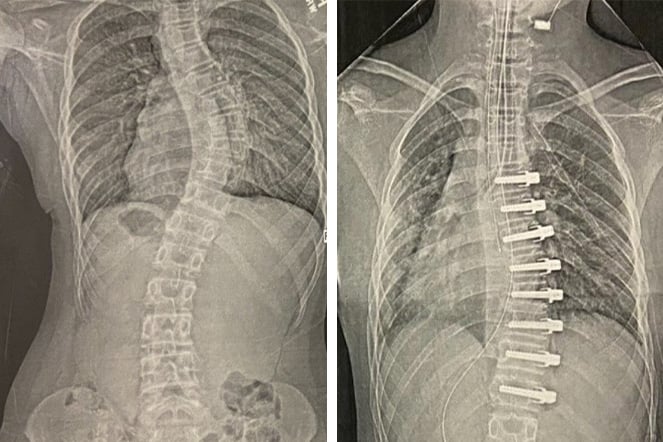

a before and after x-ray of a spine

X-rays of Abagail's spine before and after three very consistent years of bracing.

Pediatric Orthotic and Prosthetic Services (POPS) team members worked closely with her physician, Stephen Mendelson, M.D. When Abagail was diagnosed with scoliosis, he began researching advanced brace styles. Over the course of her treatment, Abagail wore three different TLSO designs. The most successful was a custom-designed brace. It reduced her curve by over 50% in-brace, an extraordinary result.